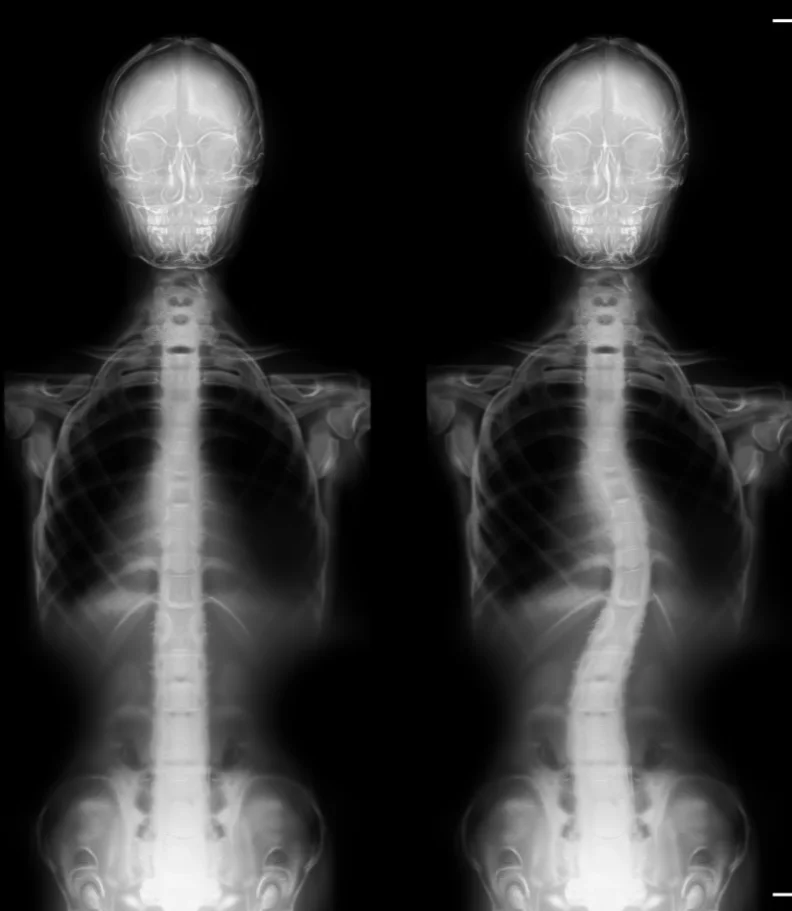

Are you in search of the finest chiropractor in Los Angeles, CA dedicated to caring for scoliosis? Typically, scoliosis begins as a subtle curvature in the spine that gradually intensifies over time. A scoliosis diagnosis occurs when the spine deviates more than ten degrees to either the right or left when facing a medical examiner. As scoliosis advances to more severe stages, it can bring about significant health consequences.

The reassuring news is that when spinal curvature is detected early and chiropractic care is sought, it can be halted from progressing into a debilitating condition. Our team of chiropractors are trained to conduct comprehensive examinations to identify scoliosis. Once diagnosed, the chiropractor conducts a detailed health history assessment to identify any contributing factors. This assessment guides the selection of the most appropriate treatment for the specific case.